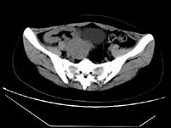

- 单项选择题女,24岁, 近日尿频明显,CT检查如图所示, 最可能的诊断是 ( )

A、膀胱癌

B、子宫肌瘤

C、卵巢癌

D、盆腔纤维瘤

E、卵巢囊肿